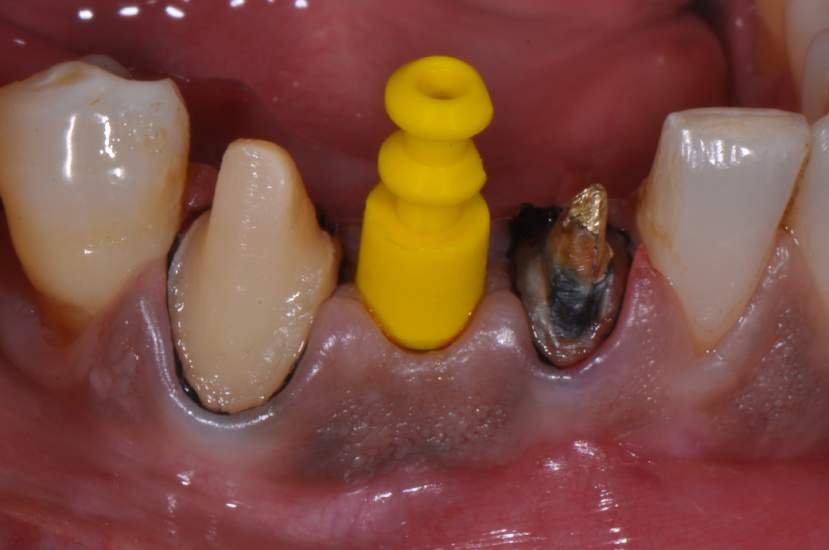

Os implantes Slim Pilar, apresentam alta versatilidade protética possibilitando aplicação de coroas Cimentadas ou Parafusadas (Fig. 3). O Sistema protético é simplificado, utilizando o mesmo sistema aplicado em implantes Implacil Cone Morse para transferentes, coifas e análogos. E a aplicação é tanto para elementos Unitários como para Múltiplos.

CASO CLÍNICO

Paciente com perda do incisivo central inferior do lado direito, utilizando uma prótese fixa em zircônia com estética e adaptação deficientes.